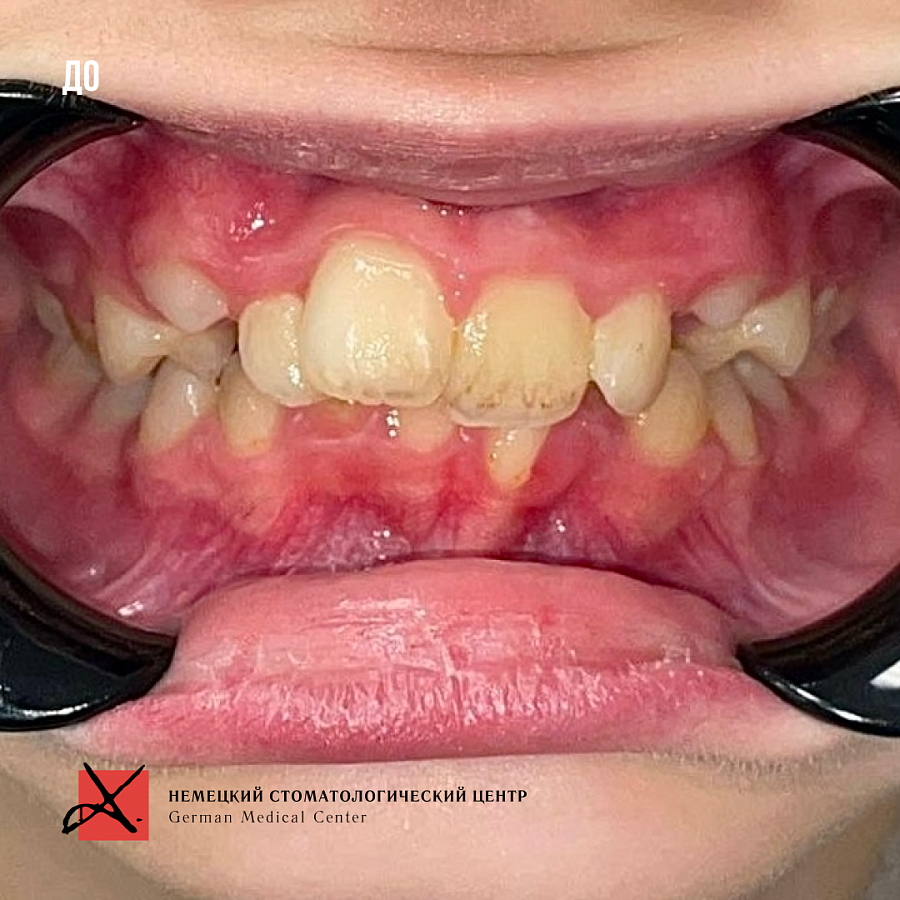

Пациентке 9 лет. Имеется ряд проблем:

- ротация верхней челюсти

- скученное положение зубов

- глубокая окклюзия

Изменения отлично видны на фото: положение зубов значительно изменилось. Зубки теперь растут ровными рядами.